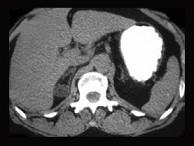

肾上腺皮质腺瘤患者,已行腺瘤切除术,术后使用可的松替代治疗的时间多为 ( )A、1~2年B、长期C、1~6个月D、6~12个月E、1个月

问题 肾上腺皮质腺瘤患者,已行腺瘤切除术,术后使用可的松替代治疗的时间多为 ( )

选项 A、1~2年 B、长期 C、1~6个月 D、6~12个月 E、1个月

答案 D